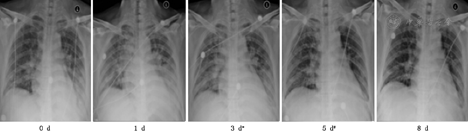

由疾控中心专业人员采样留取两份呼吸道标本(鼻咽分泌物及深部痰)作病毒核酸检测,雾化治疗后1~4 d,4例患者第1次病毒核酸检测转阴,分别间隔24 h以上再次阴性后解除隔离,详见表2。治疗后患者咳嗽、咳痰、胸闷等呼吸道症状及发热等症状逐渐好转,详见表3。呼吸频率、血常规及血气分析均恢复正常,详见表4。复查胸部影像X线检查,肺部原发病灶均逐渐吸收好转,均无新发病灶,详见图1,图2,图3,图4。

注:*表示第一次咽试子及深部痰病毒核酸检测转阴,#表示第二次咽试子及深部痰病毒核酸检测转阴(以下相同)